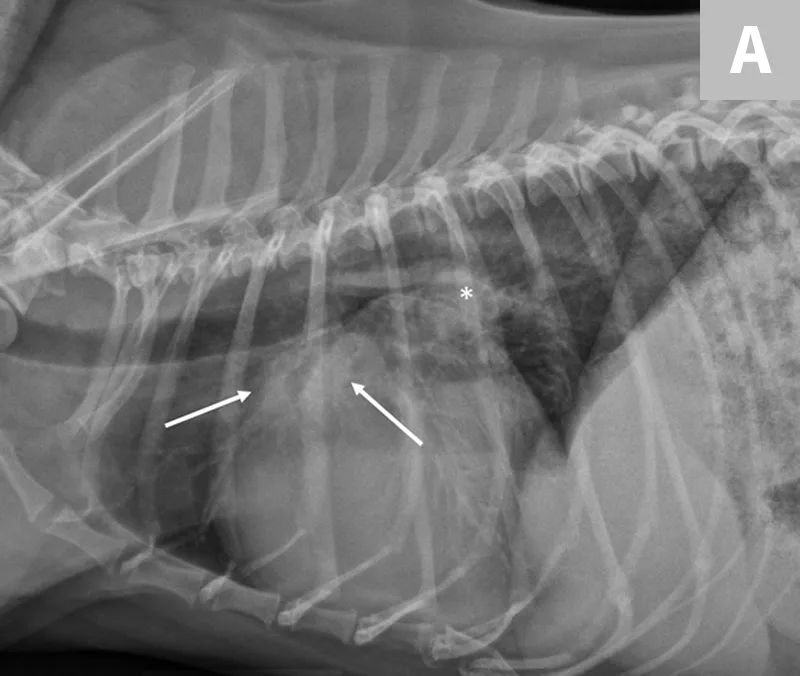

If clinical signs are not immediately life-threatening, at a minimum, a lateral thoracic radiograph should be obtained. Thoracic radiography is the gold standard for diagnosing pulmonary edema and venous congestion secondary to L-CHF.3,5 If the patient is not in distress, a 3-view study with a ventrodorsal or dorsoventral (VD/DV) view and opposite lateral thoracic views is ideal. Characteristic findings of cardiogenic pulmonary edema include increased interstitial-to-alveolar infiltrates of the perihilar and/or caudodorsal lung field in dogs.3,5 (See Figures 1A and 1B.)

FIGURE 1

(A) L-CHF in a Cavalier King Charles spaniel with mitral valve disease. Enlarged cranial lobar vessels are marked by the arrows. Enlarged left atrium is marked with an asterisk. (B) DV projection shows a caudal interstitial-to-alveolar pattern with air bronchograms (arrow). Images courtesy of University of Florida Small Animal Hospital

Left atrial enlargement is typically present in both cats and dogs with L-CHF. In dogs, left atrial enlargement typically appears in radiographs as a rounded increased opacity caudal to the carina in the perihilar region on the lateral projection. (See Figure 1A.) Generalized cardiomegaly is identified by measuring vertebral heart score (VHS).3,5 (See Figure 3.) In cats, both generalized cardiomegaly and left atrial enlargement are more difficult to assess because of their more subtle radiographic changes; they are characterized by a VHS score greater than 8 and the presence of a valentine-shaped heart on the VD/DV projection, respectively. However, normal left atrial size on thoracic radiography does not rule out the presence of L-CHF in dyspneic cats.1 Once acute L-CHF has been identified and treated, evaluation by a cardiologist is recommended, but stabilization of the patient is the first priority.